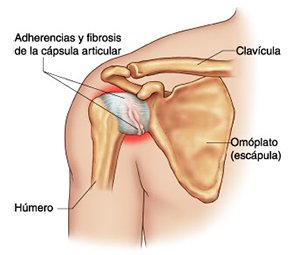

En anatomía humana, el hombro es la parte del cuerpo donde se une el brazo con el tronco. Está formado por la conjunción de los extremos de tres huesos: la clavícula, la escápula y el húmero; así como por músculos, ligamentos y tendones.

La principal articulación del hombro es la que une la cabeza del húmero con la escápula, recibe el nombre de articulación escapulohumeral y presenta dos superficies articulares, una de ellas corresponde a la cabeza del humero que tiene forma semiesférica y la otra es la cavidad glenoidea de la escápula, estas superficies están recubiertos por cartílago que permiten un movimiento suave e indoloro.

Exteriormente una envoltura de tejido blando circunda el conjunto, es la llamada cápsula articular que está reforzada por varios ligamentos que le dan estabilidad e impiden que los huesos se desplacen más allá de sus límites fisiológicos. Un conjunto de músculos y sus tendones se unen a las superficies de los huesos y hacen posible la movilidad de la articulación, entre ellos es muy importante el manguito rotador formado por cuatro músculos que proporcionan movilidad y estabilidad al hombro.